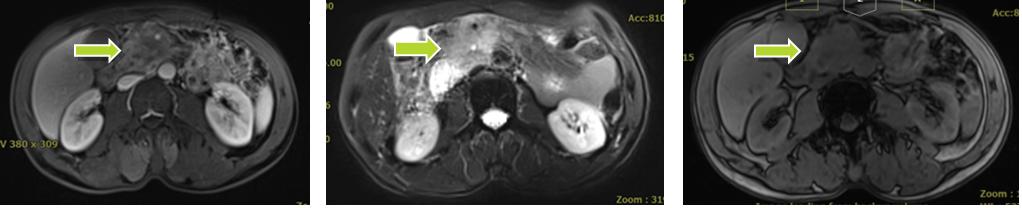

张XX,男,56岁,主诉:间断上腹部胀痛8月,恶心、呕吐10天。入院评估:腹部核磁(2020-12):胰腺钩突部及邻近肠系膜动静脉周围肿块,肠系膜上静脉受侵闭塞,十二指肠水平部压迫及狭窄。临床诊断为:1.胰腺勾突部腺癌;2.十二指肠水平部梗阻;3.重度营养不良;4.胃潴留。

碳离子治疗前患者胰腺病灶